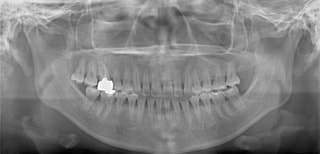

検査時パノラマレントゲン

全体の歯根のパラレリング(平行性)は悪い状態ではありません。顎関節の変形などはありません。鼻閉もありません。

成人の反対咬合なので、少し顎関節にダメージはありますが、重症ではありません。CO(中心咬合位)の位置には問題があります。CO-CRのズレが存在しますので、顎関節には負担がかかっています。